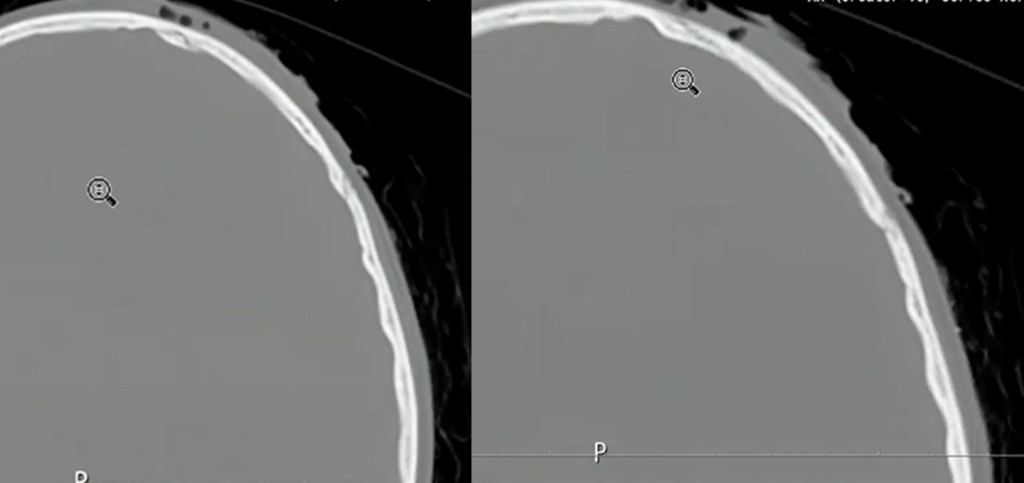

次に骨条件です。

受傷部には皮下気腫も伴っています。目立った出血や骨折はなさそうに見えます。

これを踏まえて、もう一度、骨条件の画像を確認しました。

一見すると異常が分かりにくい画像でも、3D画像を確認することで骨折の存在が明確になりました。

小児は骨が柔らかいため、外板のみが折れて陥没し、完全骨折に至らず所見が目立ちにくいことがあります。出血も初期は少量で、時間経過とともに明瞭化しました。本症例は外傷性陥没骨折、外傷性くも膜下出血・硬膜下血腫、脳挫傷と診断されました。